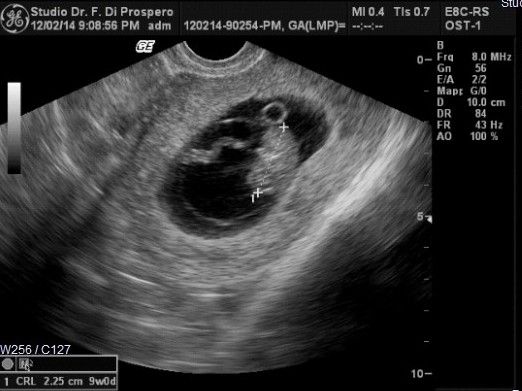

اگر سونوگرافی هفته ۸ را انجام نداده اید, احتمالا سونوگرافی هفته نهم برای محاسبه سن بارداری برای شما برنامه ریزی می شود. اگر از تاریخ آخرین پریود خود مطمئن نیستید, سونوگرافی در این هفته می تواند تاریخ فرضی شما را مشخص کند.

بسته به بارداری هر فرد, پزشک متخصص ممکن است سونوگرافی زودهنگامی را در هفته 9 ام پیشنهاد کند.

اگر این اولین سونوگرافی شما باشد, شانس فهمیدن زمان قطعی زایمان را خواهید داشت مخصوصا اگر از تاریخ آخرین پریود خود مطمئن نباشید.

سونوگرافی در هفته 9 می تواند از طریق واژن یا به صورت خارجی بر روی شکم انجام گیرد.

در سونوگرافی هفته نهم چه چیزهایی دیده می شود؟

در هفته نه شما قادر به دیدن سر, بدن و دست و پای فرزند خود هستید و ممکن است برای اولین بار قادر به شنیدن ضربان قلب رویان خود با مانیتور داپلور هستید. ممکن است لحظه ای بسیار احساسی برای شما باشد پس بهتر است به همراه خود دستمال کاغذی ببرید.

ویژگی های رویان در هفته نه

اندازه رویان در هفته نهم تقریبا 2.5 سانتی متر است.

رویان شبیه زیتون سبزی است که کمتر از 2 گرم وزن دارد

چشمان رویان رشد کرده و بزرگ تر شده و حتی رنگ هم دارد اما چشمهایش توسط پلک ها بسته هستند.

در این هفته همچنین می توانید ابتدای تشکیل انگشتان دست و پا را ببینید.